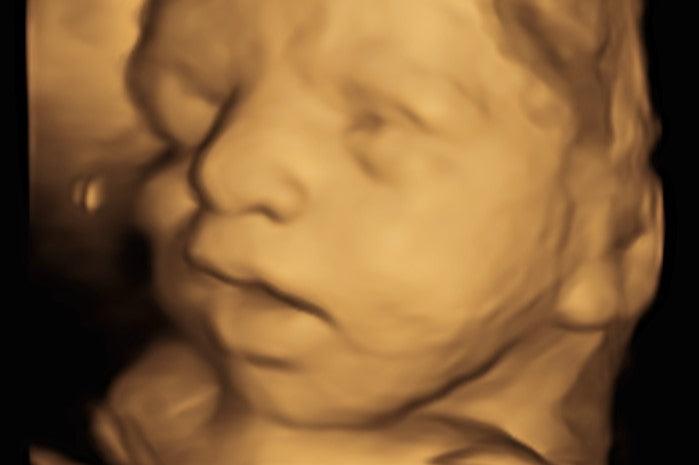

4D ultrazvuk predstavlja vrhunac moderne ultrazvučne dijagnostike, omogućavajući roditeljima ne samo da posmatraju svoje dete u realnom vremenu, već i da dobiju trodimenzionalni prikaz sa prikazom pokreta u stvarnom vremenu. Uz 4D ultrazvuk, roditelji imaju priliku da vide prve pokrete bebe, mimiku i osmeh, što je za mnoge neprocenjivo iskustvo.

Napredna 4D funkcionalnost: Aparat omogućava 4D prikaz koji prikazuje pokrete bebe u realnom vremenu, pružajući roditeljima priliku da posmatraju izraze lica i pokrete fetusa.